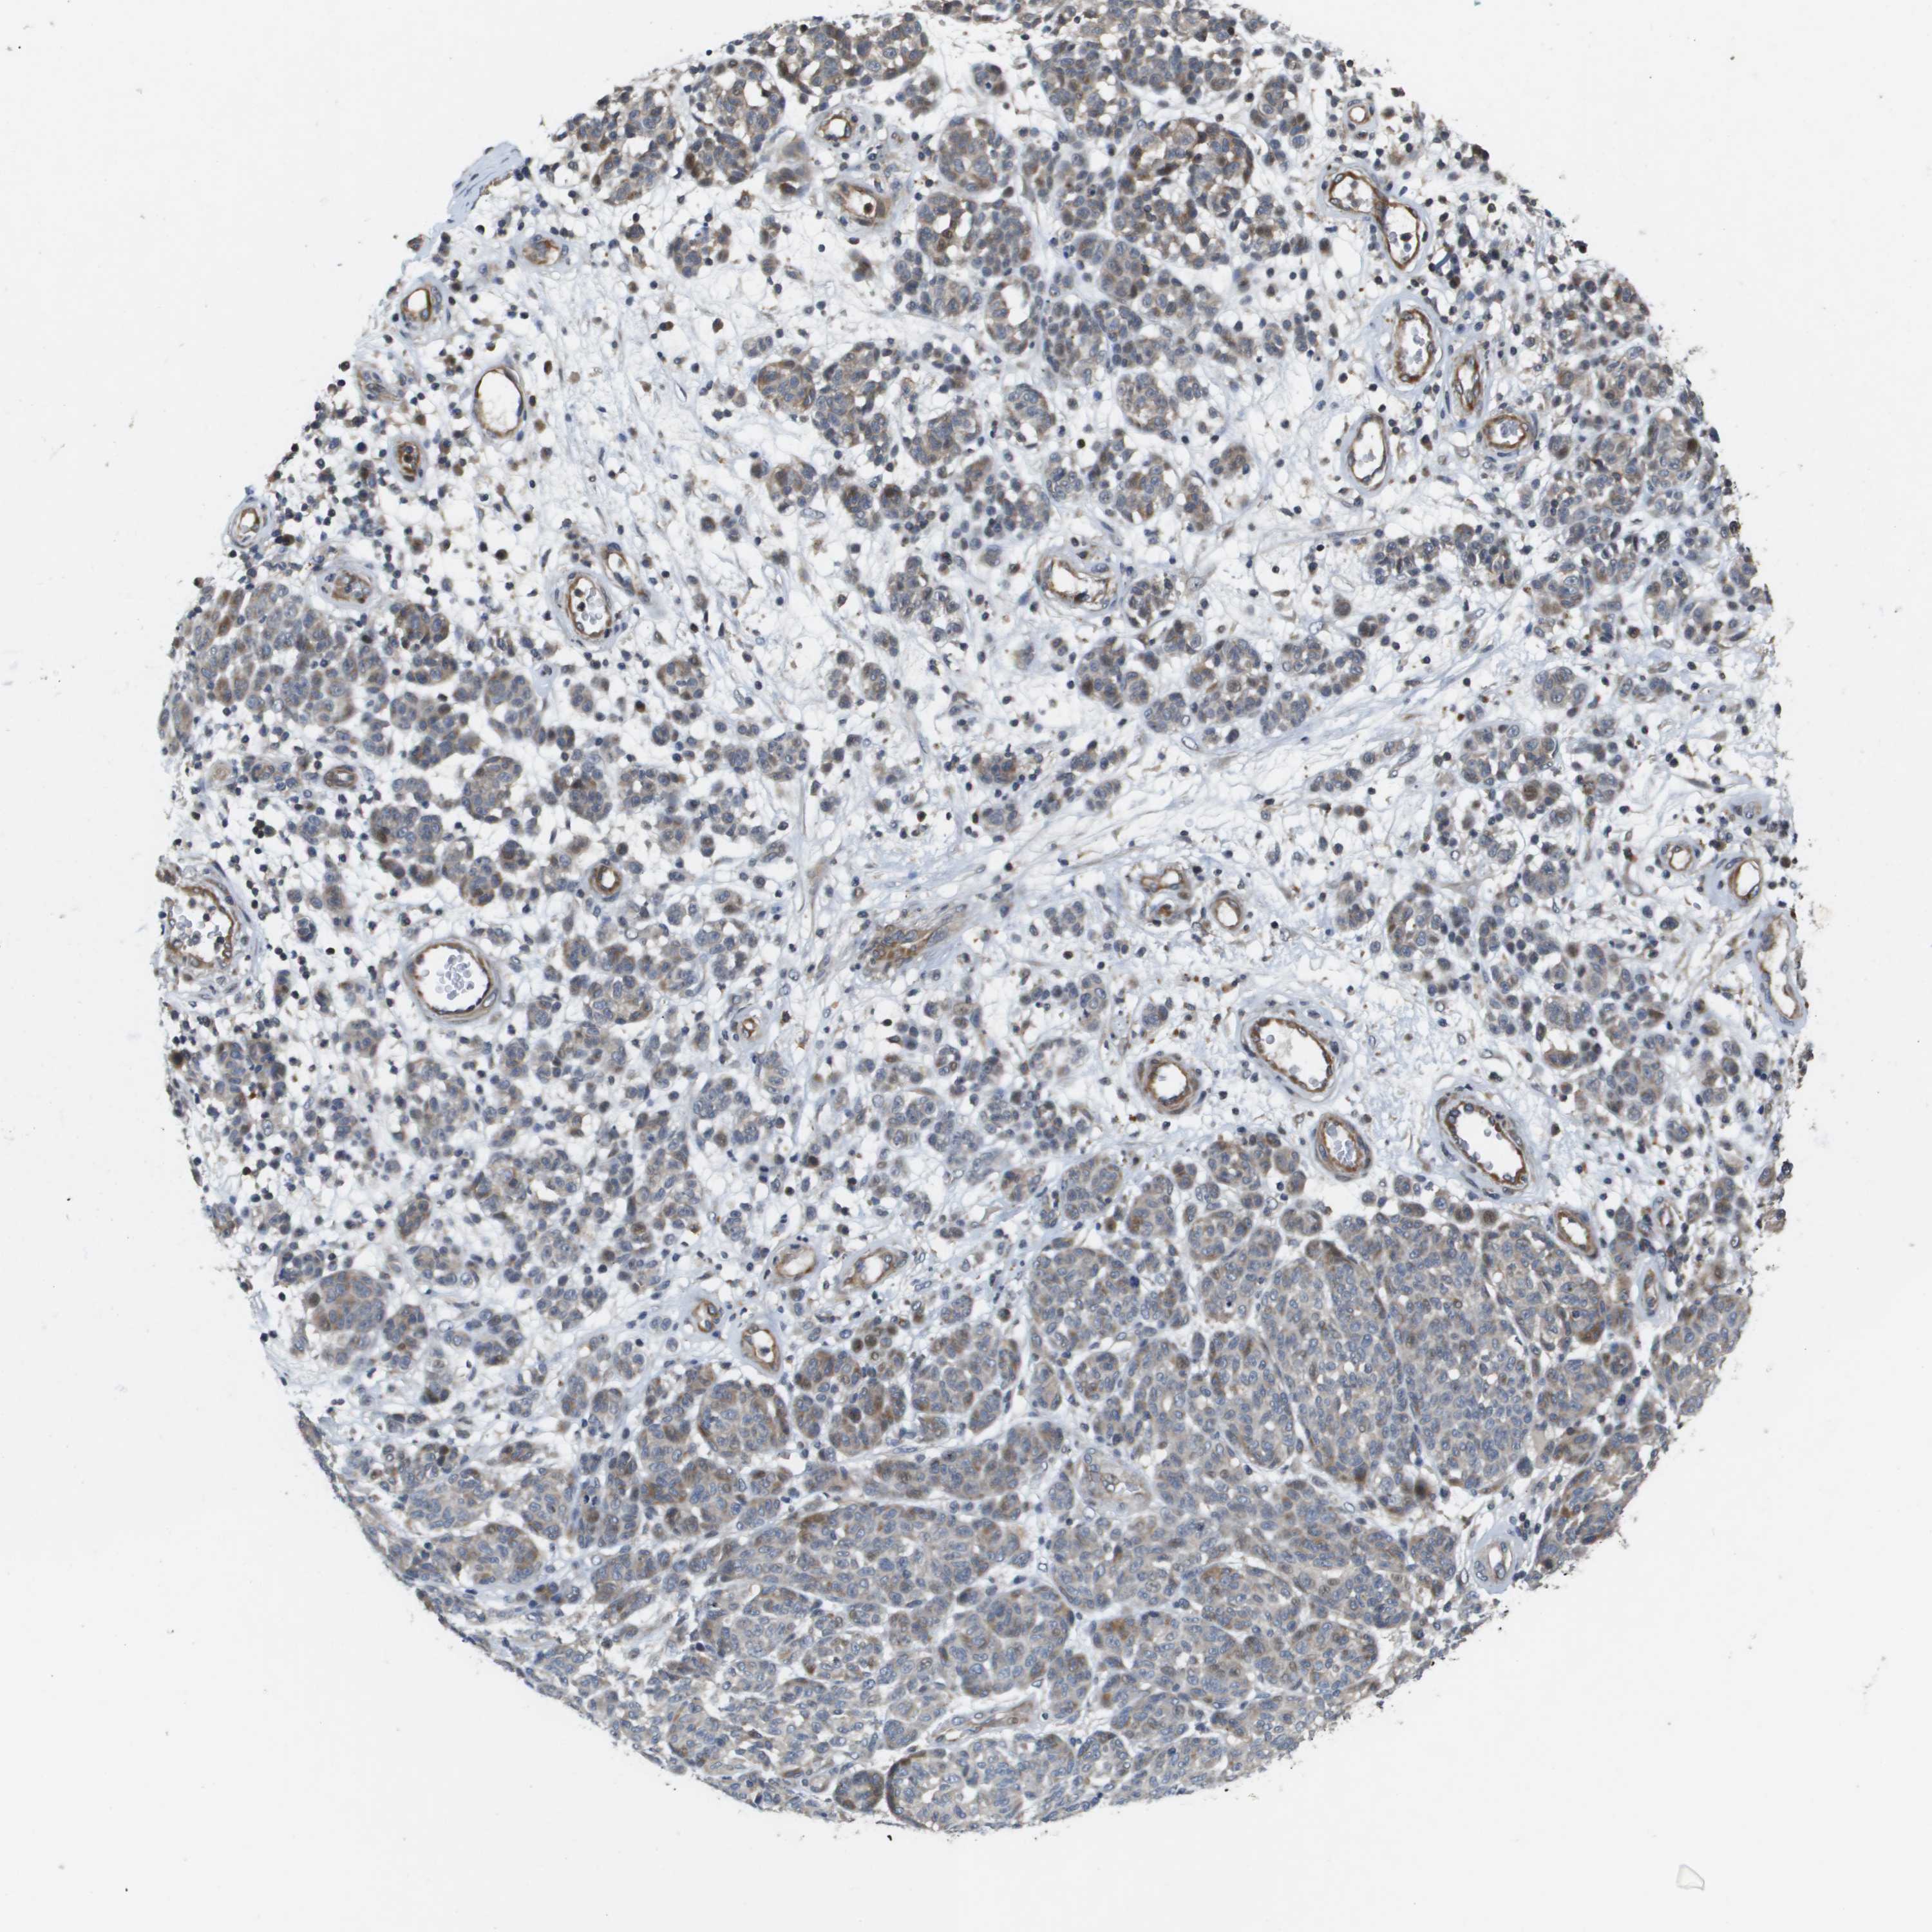

MELANOMA - Protein expressioni

A mouse-over function shows sample information and annotation data. Click on an image to view it in a full screen mode. Samples can be filtered based on level of antibody staining by selecting one or several of the following categories: high, medium, low and not detected. The assay and annotation is described here.

Note that samples used for immunohistochemistry by the Human Protein Atlas do not correspond to samples in the TCGA dataset.

Antibody stainingi

Antibody staining in the annotated cell types in the current human tissue is reported as not detected, low, medium, or high, based on conventional immunohistochemistry profiling in selected tissues. This score is based on the combination of the staining intensity and fraction of stained cells.

Each image is clickable and will lead to virtual microscopy that enables deeper exploration of all samples and also displays staining intensity scores, fraction scores and subcellular localization as well as patient and tissue information for each sample.

Antibody HPA017293

Staining

High

Medium

Low

Not detected

Intensity

Strong

Moderate

Weak

Negative

Quantity

>75%

75%-25%

<25%

None

Location

Nuclear

Cytoplasmic/membranous

Cytoplasmic/membranous,nuclear

Malignant melanoma, NOS

Malignant melanoma, Metastatic site